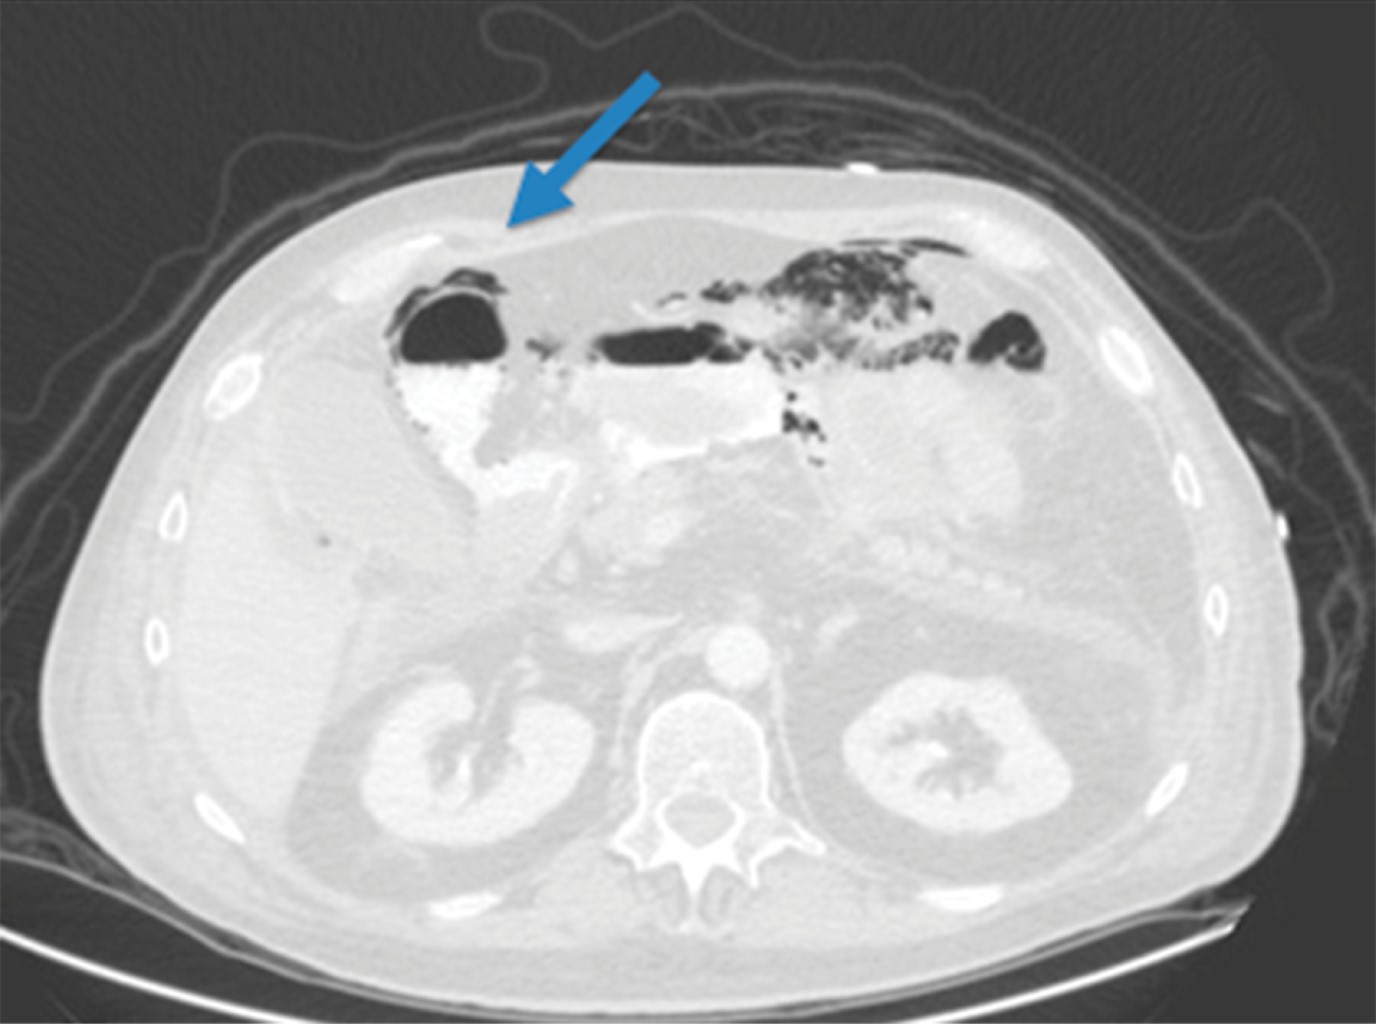

Durante el abordaje se realizaron pruebas de laboratorio (Tabla 1) y una tomografía de abdomen con doble contraste (Figura 1), en la cual se hizo evidente la salida de material de contraste hacia la cavidad abdominal a nivel de la primera porción del duodeno y abundante aire libre.

Figura 1